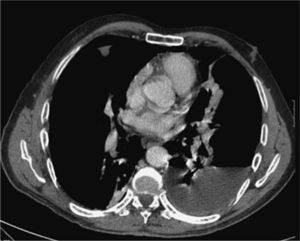

Como antecedente personal presentó hidroneumotórax izquierdo en el año 2002 secundario a posible rotura de ampolla, que requirió drenaje torácico. En la tomografía computarizada (TC) torácica se objetivaron unos nódulos de predominio subpleural bilateral (interpretados como ampollas) y derrame pleural, cuyo estudio microbiológico y citológico fue negativo. Ingresó en agosto de 2006 por presentar intenso dolor torácico derecho y disnea. La radiografía de tórax mostró un neumotórax derecho prácticamente completo e hidroneumotórax parcial izquierdo, por lo que se pensó en una nueva rotura de ampolla como había ocurrido en el año 2002. Se decidió colocar un tubo de drenaje torácico en el neumotórax derecho, con buena reexpansión pulmonar, aunque a las 48 horas presentó recidiva del neumotórax. Se descartó obstrucción mecánica del drenaje, y se confirmó la rotura de un nuevo nódulo cavitado que precisó nuevo drenaje. El líquido pleural era un exudado, según los criterios de Light, con cociente de proteínas pleurales/proteínas séricas mayor de 0,5, un cociente de LDH pleural/LDH sérica mayor de 0,6, con LDH de 2.014 U/l, ADA de 54,3 unidades y cultivo para micobacterias negativo. Sin embargo, en dicho líquido creció Aspergillus fumigatus, por lo que se inició de inmediato tratamiento antifúngico. En la analítica presentaba elevación del factor reumatoide con los demás parámetros normales. Se produjo un empeoramiento clínico del paciente, que presentó intenso dolor torácico bilateral, disnea e insuficiencia respiratoria, con saturación de O2 del 79%. Se realizó una nueva TC torácica, que mostró un hidroneumotórax izquierdo que había evolucionado respecto a la imagen radiológica, con atelectasia casi completa del pulmón subyacente y neumotórax derecho, reducido a una fina lámina, con imagen de enfisema subcutáneo asociado (fig. 1). Se apreciaron nódulos pulmonares parenquimatosos, la mayoría subpleurales y menores de 1cm de diámetro, además de adenopatías de carácter inespecífico, de centro graso y aspecto benigno en huecos axilares, cadenas paratraqueales y subcarinales. Por falta de mejoría clínica, tras una semana de tratamiento con soporte respiratorio, tubo de drenaje y tratamiento antifúngico, fue trasladado a cirugía torácica para tratamiento quirúrgico inmediato. En las muestras obtenidas se cultivó A. fumigatus y la biopsia de los nódulos descritos en la TC correspondieron histológicamente a nódulos reumatoideos, descartándose la presencia de ampollas.